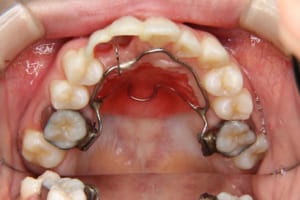

治療中

使用した装置 マルチブラケット装置(唇側矯正)

InVuブラケット

シルバーワイヤー

ホールディングアーチ

歯科矯正用アンカースクリュー(1本)

牽引に半年かかりました。